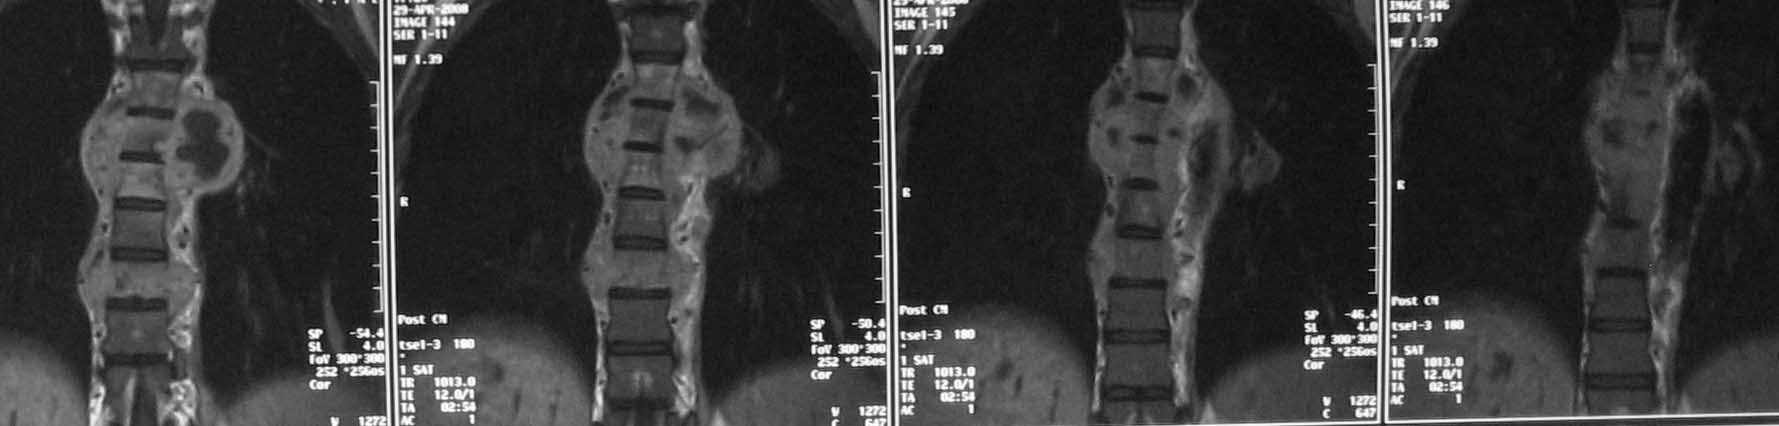

30-летняя женщина с постоянными болями в грудном отделе позвоночника, резко усиливавшимися при переходе в вертикальное положение,

в течение 3 месяцев получала конервативное лечение по поводу "остеохондроза". около 3 недель назад возникла резкая слабость в ногах, задержка стула и мочеиспускания. КТ, МРТ и торакоскопичсекая биопсия с посевом выявили хронический стафилококковый спондилодицит грудного отдела позвоночника. Клинически отмечается болевой синдром, невозможность вертикализации пациентки из-за боли, нижний спастический парапарез (мышечная сила до 3 баллов, стойкая задержка мочи и стула. Соматически компенсирована, лихорадка субфебрильная, лабораторный признаки воспаления выражены умеренно.Хотелось бы услышать ваше мнение, уважаемые коллеги, по поводу объема операции и инструментации.